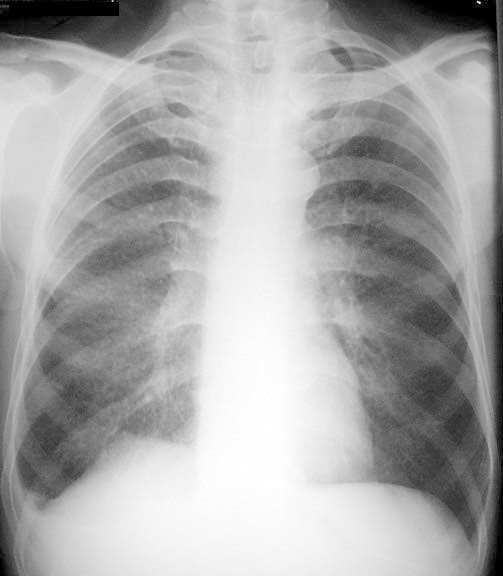

Silicosis

• Miliary nodules

• Blunting of right costophrenic angle

Close up view below.